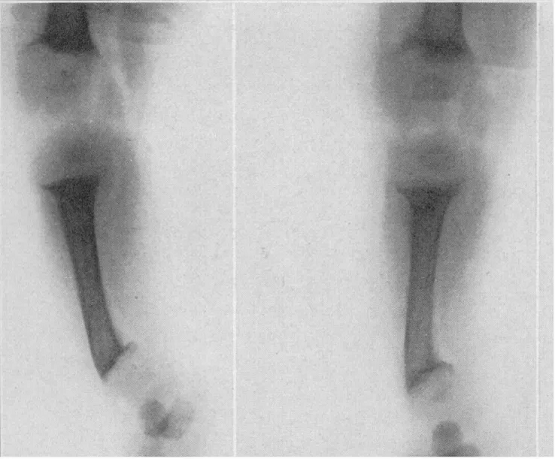

图2 | 儿童佝偻病X光片

欧洲临床医生推荐鱼肝油治疗佝偻病

“佝偻病”这个名字来自“wrickken”一词,在古英语中,它的意思是“扭曲”。

由于工业革命时期缺乏维生素D,佝偻病被称为“英国病”,在城市贫困儿童中流行。

·在德国,Schütte教授发表了第一个用鱼肝油治愈佝偻病的病历,并表示他已经使用了25 年。他引用的病例是3-5岁无法行走的儿童,他们在连续服用鱼肝油5-9周内治愈。